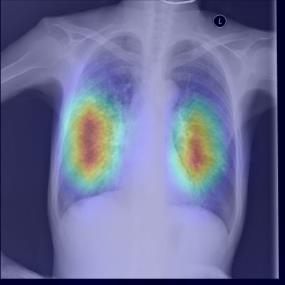

Chest X-ray (CXR) is the most typical diagnostic X-ray examination for screening various thoracic diseases. Automatically localizing lesions from CXR is promising for alleviating radiologists' reading burden. However, CXR datasets are often with massive image-level annotations and scarce lesion-level annotations, and more often, without annotations. Thus far, unifying different supervision granularities to develop thoracic disease detection algorithms has not been comprehensively addressed. In this paper, we present OXnet, the first deep omni-supervised thoracic disease detection network to our best knowledge that uses as much available supervision as possible for CXR diagnosis. We first introduce supervised learning via a one-stage detection model. Then, we inject a global classification head to the detection model and propose dual attention alignment to guide the global gradient to the local detection branch, which enables learning lesion detection from image-level annotations. We also impose intra-class compactness and inter-class separability with global prototype alignment to further enhance the global information learning. Moreover, we leverage a soft focal loss to distill the soft pseudo-labels of unlabeled data generated by a teacher model. Extensive experiments on a large-scale chest X-ray dataset show the proposed OXnet outperforms competitive methods with significant margins. Further, we investigate omni-supervision under various annotation granularities and corroborate OXnet is a promising choice to mitigate the plight of annotation shortage for medical image diagnosis.